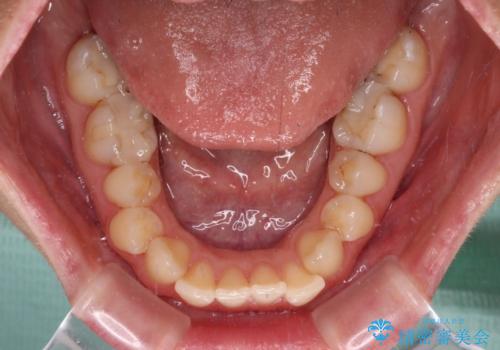

【モニター】オープンバイトをインビザライン矯正で治す

- 前歯の開咬を気にして来院された患者様です。

開咬の治療は、前歯を閉じるように動かすとともに、上下臼歯を圧下(骨内にめり込ませる)させることで進めて行きます。

インビザラインは臼歯の圧下を効果的に行えるため、インビザラインを用いて矯正治療を行うこととしました。

オープンバイトは舌の突出癖により誘発され、治療後も突出癖が残っている容易に後戻りしてしまいます。

治療期間を短縮するためにも、舌突出癖の改善が極めて重要となります。